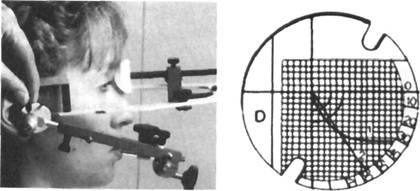

Аксиография — метод, позволяющий осуществить графическую запись траектории смешения суставной головки и диска при различных движениях нижней челюсти с помощью аксиографа. Для записи

|

Рис. 13.32. Регистрация суставного пути и его запись на миллиметровой сетке.

1 — траектория суставного пути в виде кривой. Линия смещения оси суставной головки при перемещении нижней челюсти вниз совпадает с обратным движением; 2 — первые 5 мм кривой, соотнесенные к франкфуртской плоскости, образуют угол суставного пути.

пути смешения сустава осуществляют следующие действия: 1) регистратор устанавливают острием на отметке "О" координатной сетки при наиболее ретрузионном положении нижней челюсти пациента; 2) окончательно фиксируют удерживающие зажимы и пациента просят выдвинуть нижнюю челюсть вперед, чтобы проверить наличие регистратора на регистрационной площадке. После этого путь смещения сустава может быть записан при любых движениях нижней челюсти; 3) при произвольном максимальном перемещении пациентом нижней челюсти вниз регистрируют кривую движения суставной головки и диска по заднему скату суставного бугорка (рис. 13.32).